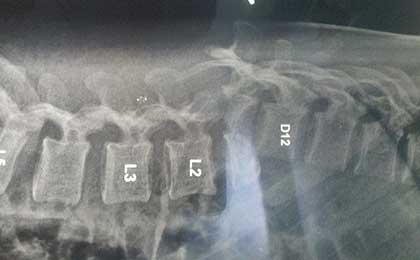

pre op xray 1

POST OP XRAY LAT

post op x ray lat 1